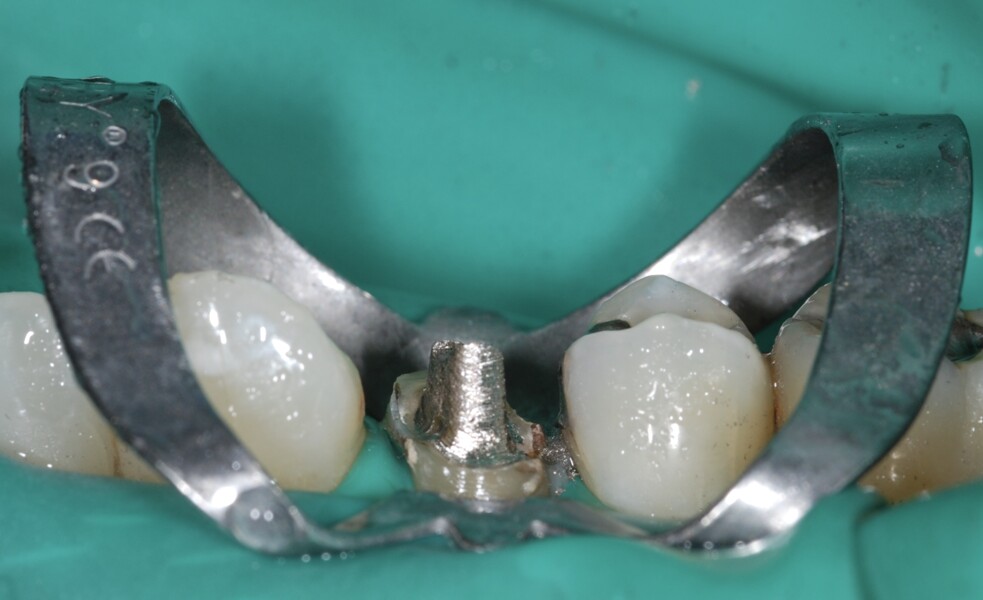

D’un point de vue pratique, la première étape consiste à réduire les dimensions du tenon s’il occupe une grande partie de la structure coronaire, de préférence en lui donnant une forme cylindrique similaire à celle d’un tenon préfabriqué. De même, une reconstitution corono-radiculaire coulée ancrée dans plusieurs canaux doit d’abord être sectionnée jusqu’au niveau du plancher de la cavité pulpaire, afin de la traiter comme un ensemble de tenons unitaires, ce qui diminue le degré de rétention global du système. La réduction du tenon doit être effectuée avec des fraises en carbure spécialement conçues pour découper le métal, sous une irrigation abondante. Les évaluations cliniques et radiographies préliminaires sont essentielles pour planifier l’angle de coupe. La procédure doit être fréquemment vérifiée et, si nécessaire, il convient d’effectuer des contrôles radiographiques avant qu’une quantité excessive de dentine ne soit sacrifiée (Figs. 1–3).

Fig. 1 : Radiographie préopératoire montrant la présence d’une reconstitution corono-radiculaire coulée, ancrée dans les trois canaux.